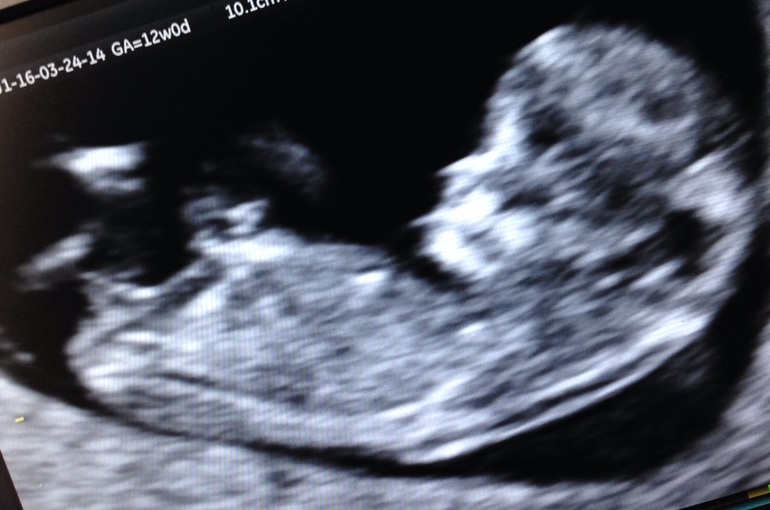

Привет девочки !) вот и я прошла 1 скрининг , конечно волновалась очень, но всё же прошло хорошо, когда врач говорил про нашу лялечку, про строения, ораны я потихоньку выдыхала )

В итоге все в норме, чсс 172 уд. Срок 11,5

Холила с мужем , врач все ему показал рассказал ( делали в жк, бесплатно ) , у нас первый сынок и я конечно мечтала и думала что будет девочка, но когда врач приблизила и показала на бугорок, говорит на таком сроке рано конечно, но предположительно мальчик ) конечно я уже люблю и мальчика, главное чтобы здоровенький , но еще малюсенькая надежда на девочку у меня остается, ну прям очень дочу хочется ) интересно у кого то на таком сроке ошибались с предположением? спасибо кто прочитал 😊 фото моей крошки )